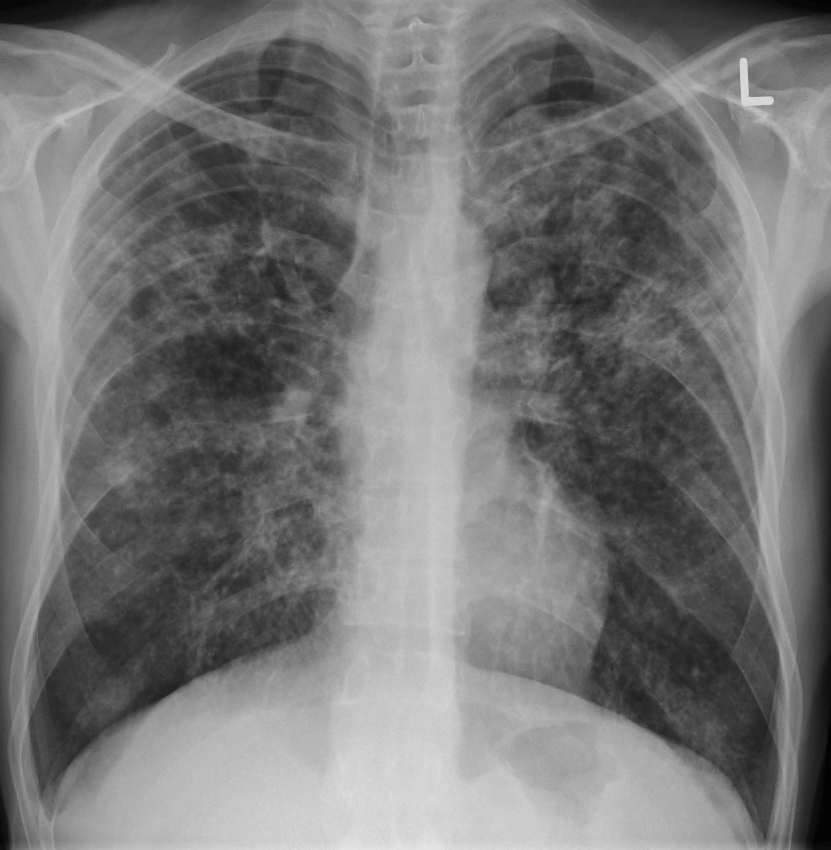

a) Miliary Tuberculosis: In immunocompromised individuals or those with high bacterial loads, the infection can disseminate throughout the body, affecting the marrow, liver, and spleen.